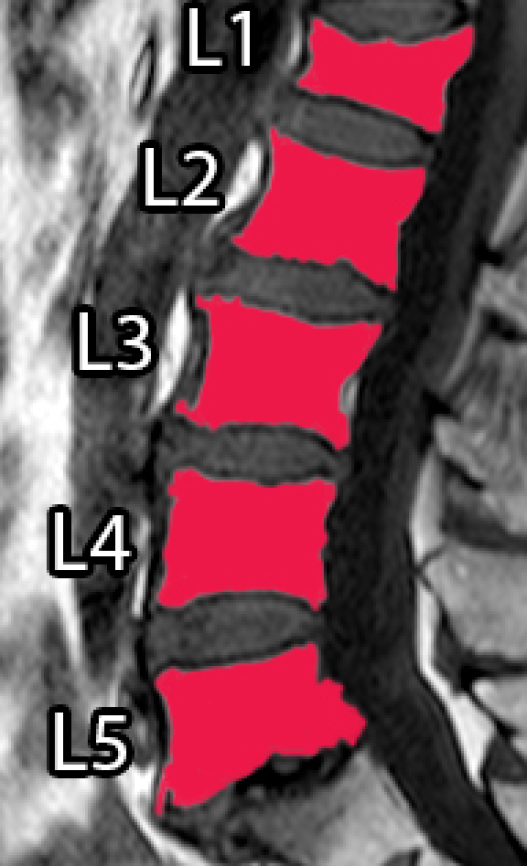

Spinal diseases are quite usual worldwide and can cause significant loss of function and quality of life [1]. A very recurrent disease among older adults is the Vertebral Compression Fracture (VCF), which, in general, is caused by osteoporosis (benign) or bone metastasis (malignant) [2, 3, 4]. In general, VCFs are early detected or diagnosed based on shape or texture using Magnetic Resonance Imaging (MRI) [5, 6, 3, 7]. Usually, a specialist manually segments the Region of Interest (ROI) to aid the diagnose, which can be time consuming and prone to errors, due to inter and intra-subject variability and the subjective judgment that is employed [8].

However, it incorporates expert knowledge gained over several years. Figure 1 shows an example of manual segmentation over five lumbar vertebral bodies (L1-L5).

![]() |

| (a) Original image | (b) Ground-truth |